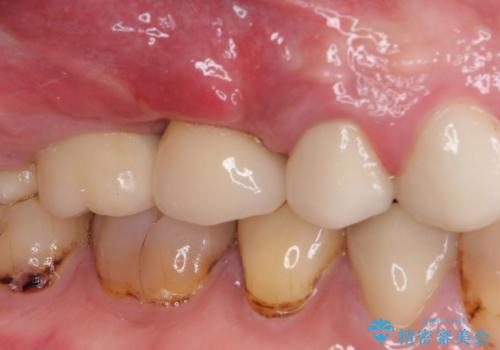

- 咬合力により歯が割れてしまった方のインプラント治療です。

抜歯後4ヶ月ほど待ち、後方のインプラントと同一メーカーのインプラントを埋入することとしました。

大変怖がりであるため、インプラント治療の際には静脈内鎮静により、眠っている間に手術を行いました。